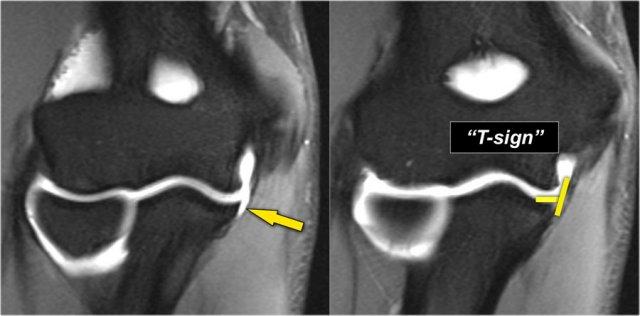

Đây là vận động viên ném bóng chày 18 tuổi với triệu chứng đau mặt trong khuỷu tay.

Có thể thấy một vết rách một phần tạo ra ‘dấu hiệu T’.

Đầu tiên hãy nghiên cứu các hình ảnh T2-fatsat theo mặt phẳng vành và sau đó tiếp tục đọc…

Lưu ý rằng bó trước còn nguyên vẹn và bám chắc vào củ sublime (mũi tên vàng).

Trên hai hình ảnh tiếp theo, có một số phù nề mô mềm và tín hiệu bất thường rõ hơn ở phía sau (mũi tên đỏ). Vì vậy, chúng tôi nghi ngờ có bệnh lý của bó sau.